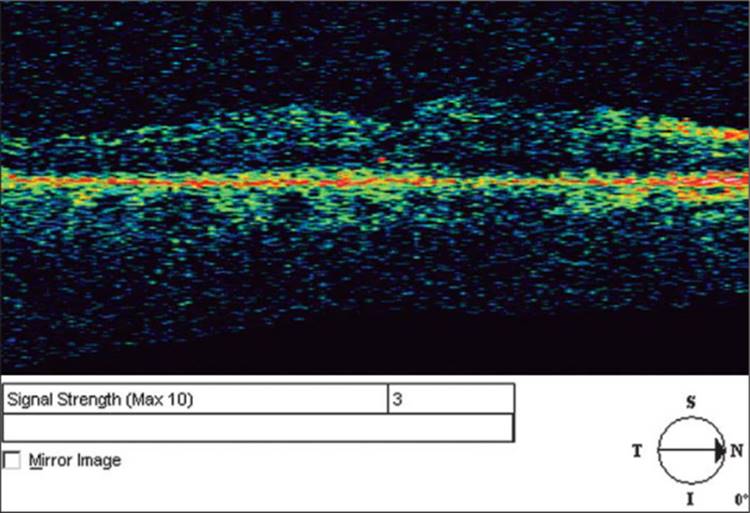

Mydriasis is not always necessary to obtain OCT but may provide a higher signal-to-noise ratio and consequently better microstructural details. Dilation also decreases the amount of 'vignetting' which is described below. Obtaining quality OCT images depends upon the light being able to reach the target tissue. If there is significant media opacification such as corneal opacification or severe cataract there will be less light reaching the posterior segment and less light returning to the inferometer for detection. This 'signal-to-noise ratio' is displayed on the screen and labeled as 'signal strength'. A signal strength of 10 represents the highest quality imaging whereas a signal strength of zero represents the lowest quality. If there is little light reaching the tissue, the images appear dull or 'washed out' and it is difficult to detect subtle abnormalities and differences in tissue reflectivity. Figure 130.4 shows an example of low signal strength. Notice how the ordinarily highly reflective structures appear blue or even black. Moderate media opacities such as early cataract, asteroid hyalosis, and mild vitreous hemorrhage do not preclude adequate imaging.[20,21] OCT can be performed through silicone oil, but not through intraocular gas.

Click to view full size figure

FIGURE 130.4 Example of low 'signal-to-noise ratio'. Notice how the entire image appears 'washed out'. It is difficult to discern details of the retinal microstructure. The signal strength is relatively low at three.